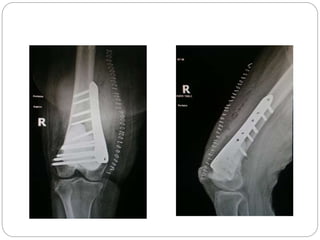

This document discusses 8 oncology cases. Case 1 involves a 40-year old female with right knee pain. Case 2 is a 28-year old male with a left subtrochantric fracture from a MVA who is now experiencing increasing left knee pain and swelling. Biopsy results showed high-grade osteosarcoma. Case 3 is a 30-year old female with breast cancer and bone metastases causing bilateral hip pain.